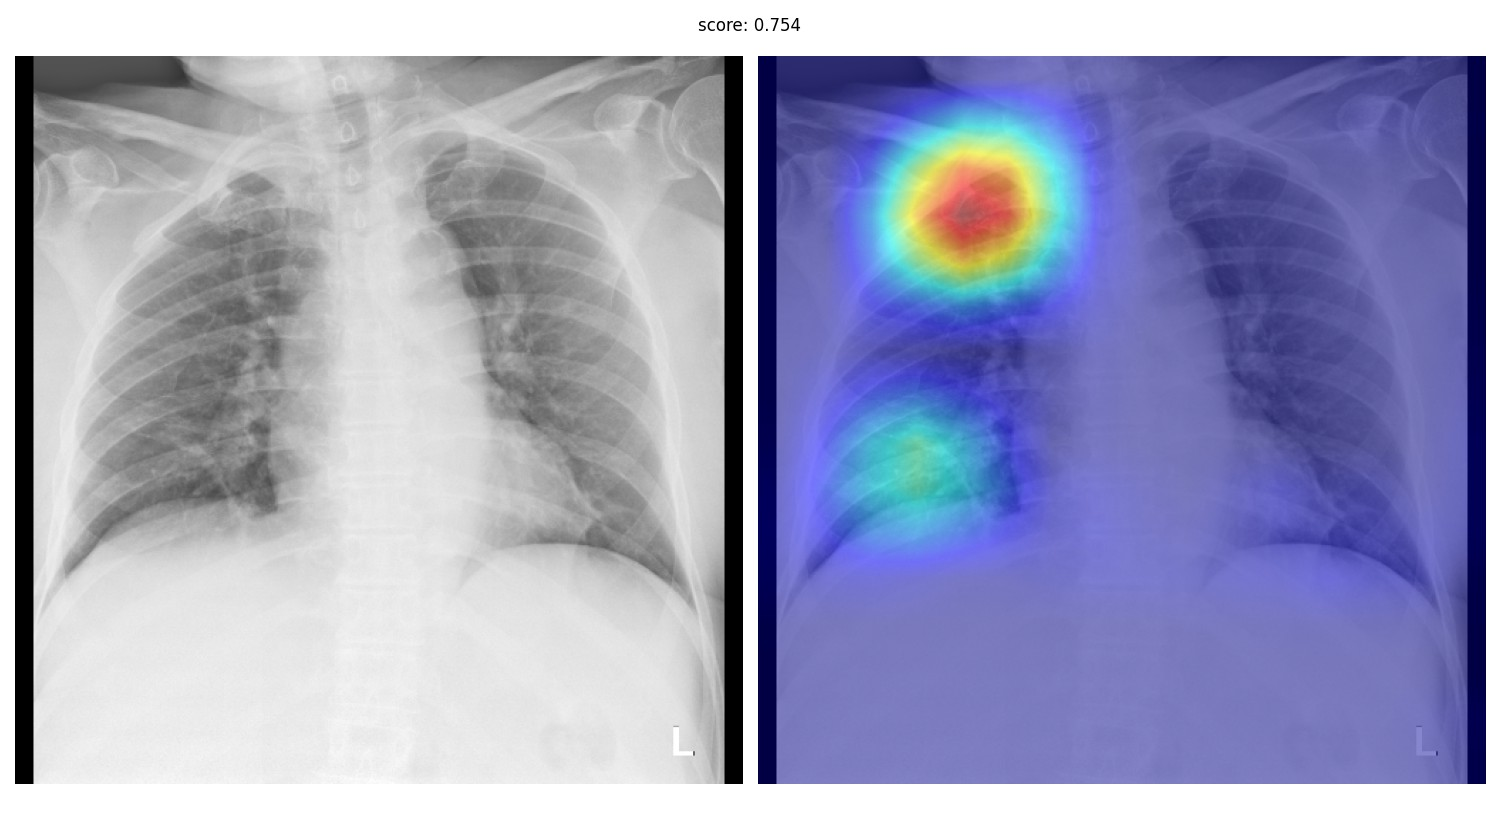

Что такое интерпретируемость, если решается задача классификации всего рентгенологического исследования - в целом понятно. Врачи не доверяют системам, которые просто говорят "тут где-то на картинке есть рак", а значит нужны какие-то методы, которые будут "объяснять" итоговое предсказание. Их придумано довольно много - разнообразные виды GradCAMа, окклюзия, LIME. Из коробки многие из них можно взять из библиотеки Captum для Pytorch.

Однако, жизнь показывает, что качество локализации клинически значимых признаков у этих методов, мягко говоря, неудовлетворительное. При этом вряд ли кто-то будет всерьёз рассматривать ИИ-систему, которая не решает задачу локализации - детекции или сегментации. Да и реально хороших метрик на чистой классификации достичь удаётся разве что при наличии очень больших, чистых датасетов. На данный момент у нас четыре системы в проде, из них одна - это детекция, две - инстанс-сегментация, и ещё одна - семантическая сегментация.